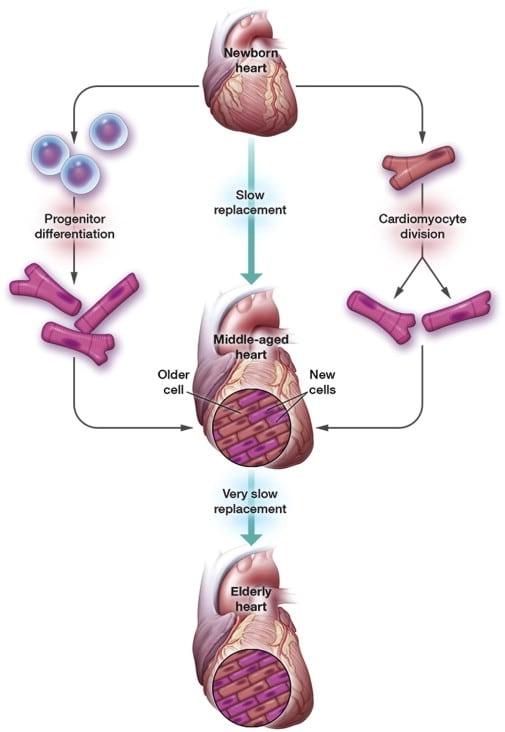

У этой гипотезы есть узкие места. Скажем, регенерация клеток сердца никак не связана с инфекциями: сердце относительно далеко от кожи, после инфаркта туда не попадет бактерия. Было бы неплохо, если бы оно нормально регенерировало. Вместо этого обычные клетки там замещает фиброзная ткань, как на поверхности кожи. То же относится к другим внутренним органам.

Человеческое сердце эффективно защищено окружающими тканями и если в нем есть открытая рана, то обладатель сердца уже умер. Зачем блокировать регенерацию такого органа — с эволюционной точки зрения непонятно. Зато понятно, что это мешает восстановлению людей после инфарктов / © Wikimedia Commons

Вопрос о том, как заставить механизм включить регенерацию обратно, научно сложный. Эксперименты по реактивации таких генов на рыбах уже дали полный успех, на мышах — частичный. Часть сердца после инфаркта удалось восстановить без «рубцов», настоящими кардиомиоцитами, то есть без снижения функций сердца. Однако полного восстановления у млекопитающих пока не происходит.